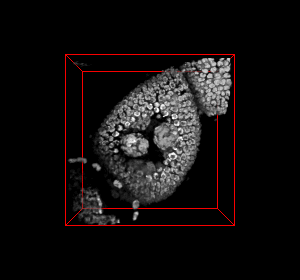

Detection, Segmentation, and Classification of Nuclear and Sub-Nuclear Structures

Understanding the 3-D spatial organization of genes and other genetic elements within the cell nucleus is important for regulating the gene expression level. The biologists are interested in quantitative methods for studying nuclear organization and sub-nuclear gene distribution. They currently lack high-throughput methods for quantitative global analysis of 3-D gene organization. The aim of this project is to build an automated system capable of detection, segmentation and classification of 3-D nucleus and the sub-nuclear 3-D spots obtained from microscopy image data. more